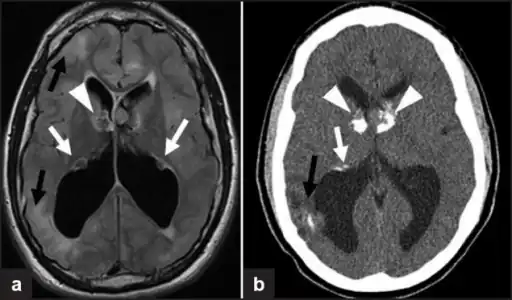

a,b)Images of subependymal giant cell astrocytomas arrowheads

Diagnosis is made by imaging with a contrast-enhanced MRI or CT scan of the brain.[3]